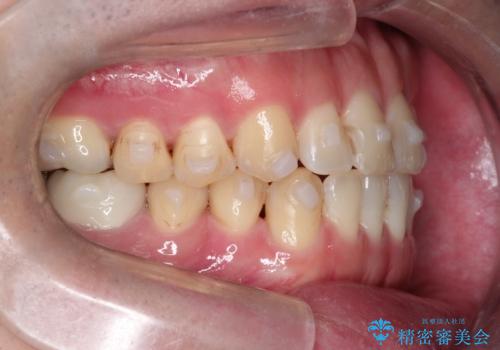

前歯が嚙んでない場合(開咬)、顎間ゴムというゴムを使用してもらうことがあります。顎間ゴムは、前歯を噛み合わせるための力を与える補助的な役割があります。

マウスピース矯正は、患者様のご協力が重要です。マウスピースをきちんと装着し、歯科医院での定期検診が必要になります。